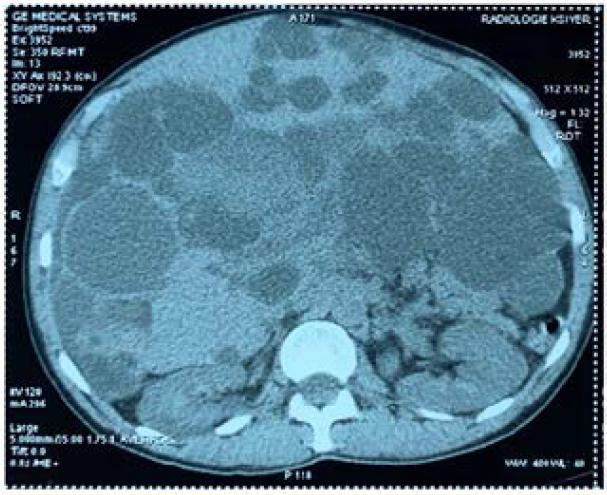

A Rare Case of Infected Isolated Polycystic Liver Disease Presenting Jaundice and Ascites

W Hliwa, I Jbara, F El Rhaoussi, M Tahiri, F Haddad, A Bellabah and W Badre. 10(4): 37-40.